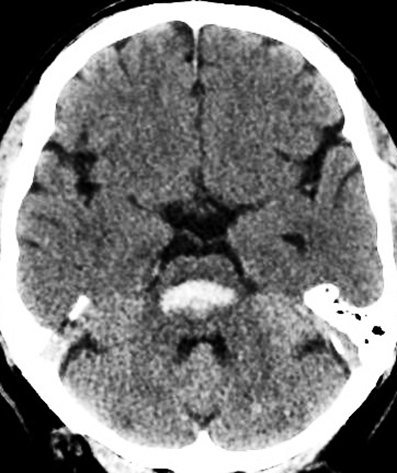

1. A 50-year-old woman with a known history of hypertension presented with an acute pontine hemorrhage, as demonstrated on computed tomography (arrow).

A. Non-contrast CT (first-line)

• Hyperdense lesion in the pons, usually in a central or paramedian location

• "Bilateral teardrop" or "butterfly" sign in extensive bleeds

• Mass effect: Compression of the fourth ventricle, hydrocephalus

• Ventricular extension may be present